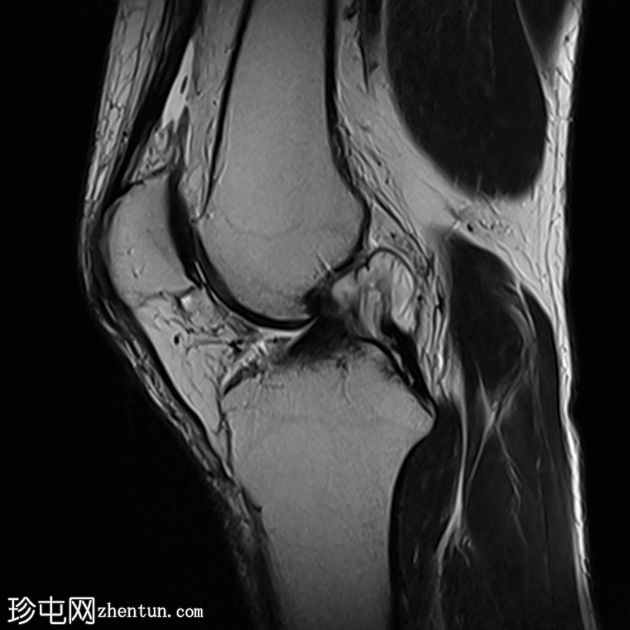

冠状面PD脂肪饱和度

T2和PD脂肪饱和序列上可见多处轻微高信号区,位于股四头肌腱远端、前交叉韧带、内侧副韧带近端1/3内表面深层、腘肌腱附着处。

少量膝关节积液。

其他发现包括:前交叉韧带腱鞘囊肿、膝关节后外侧轻度肌间液信号和轻度软骨软化。

印象:这些发现提示痛风性关节炎伴单钠尿酸盐晶体沉积。